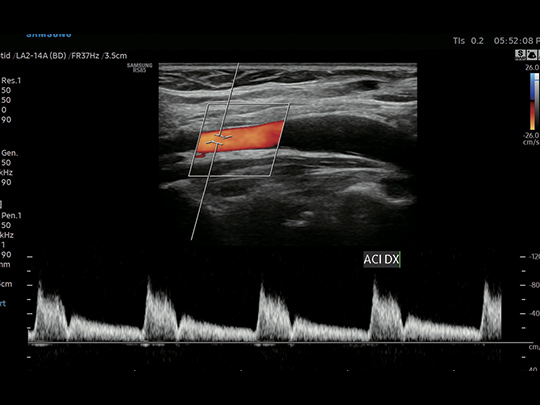

LA2-14A

- Small parts, vascular, musculoskeletal, abdomen